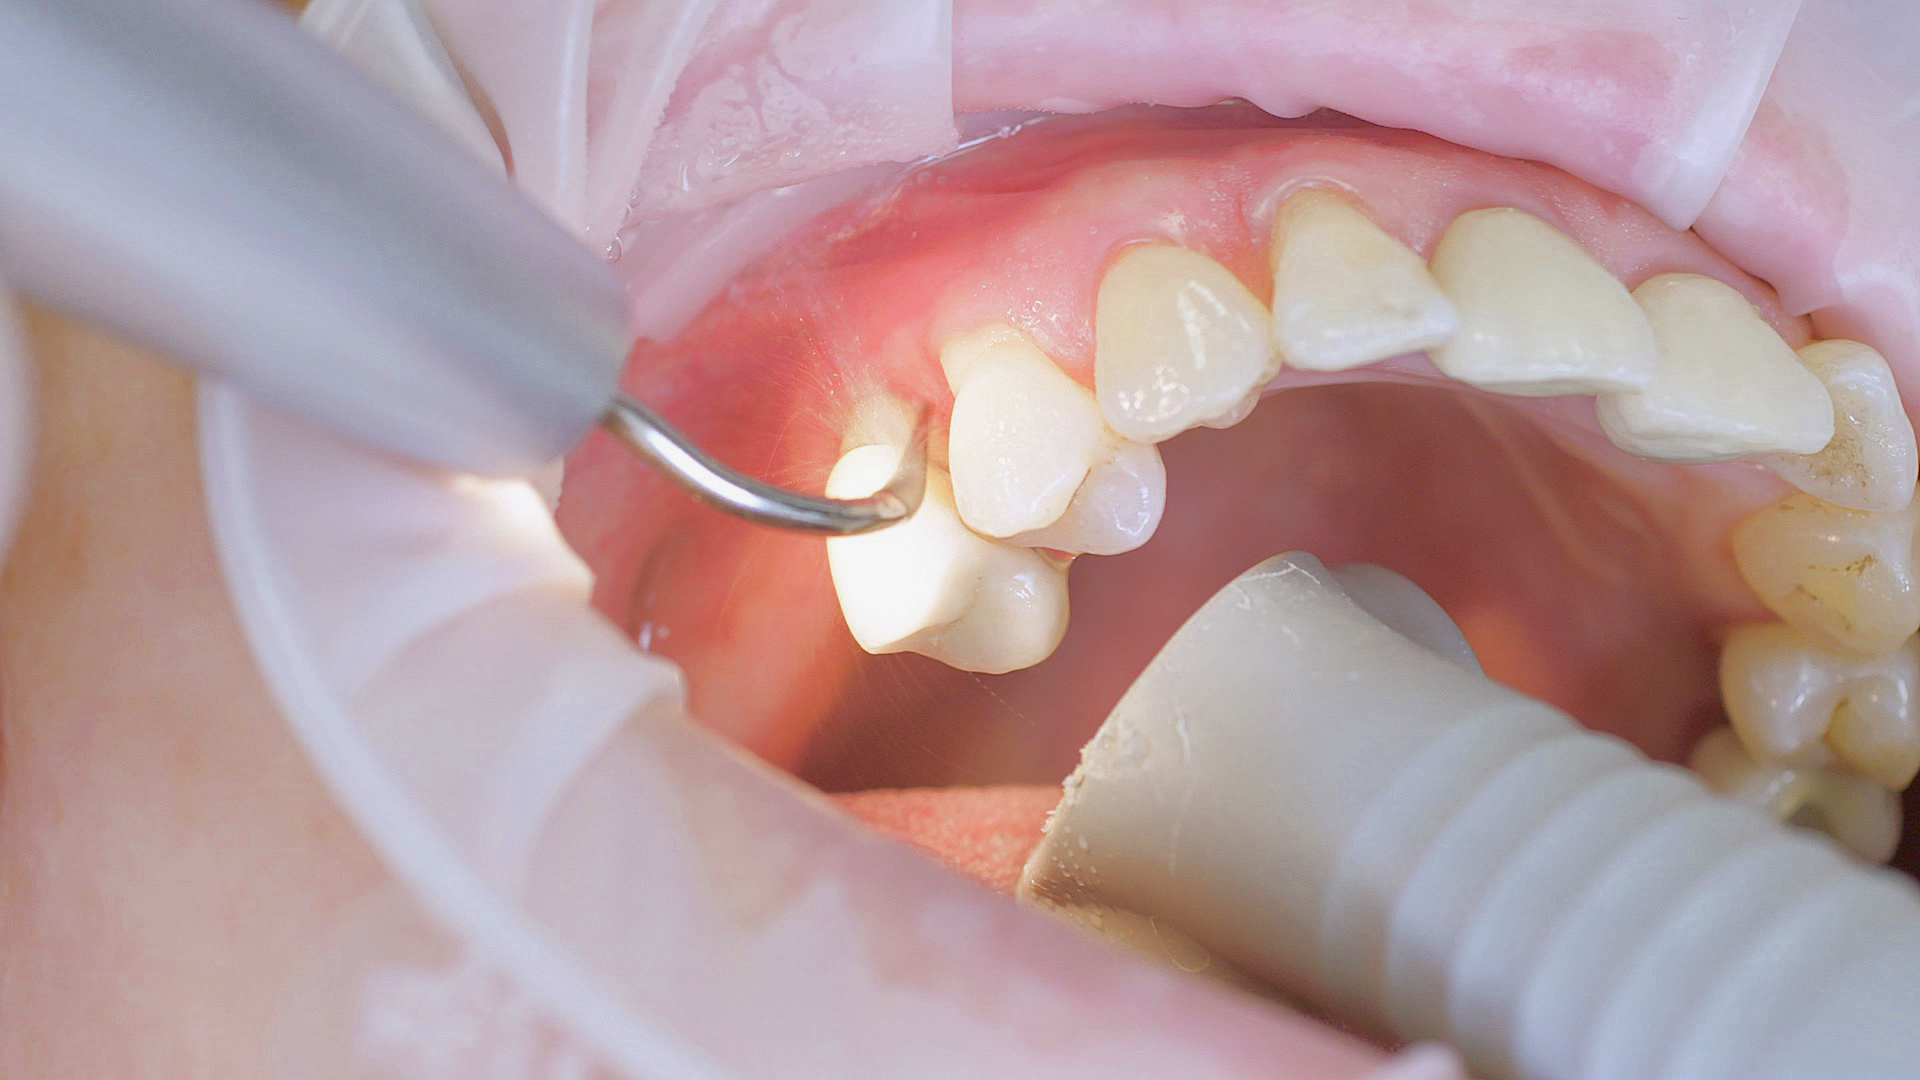

Dans les soins de suivi parodontal post-implantation, les concrétions molles (biofilm) et dures doivent être éliminées régulièrement par des techniques de nettoyage mécanique professionnelles. [16, 17] Dans les zones subgingivales et supragingivales, on utilise généralement pour cela des dispositifs à ultrasons (Fig. 4) en combinaison avec des instruments manuels si nécessaire.